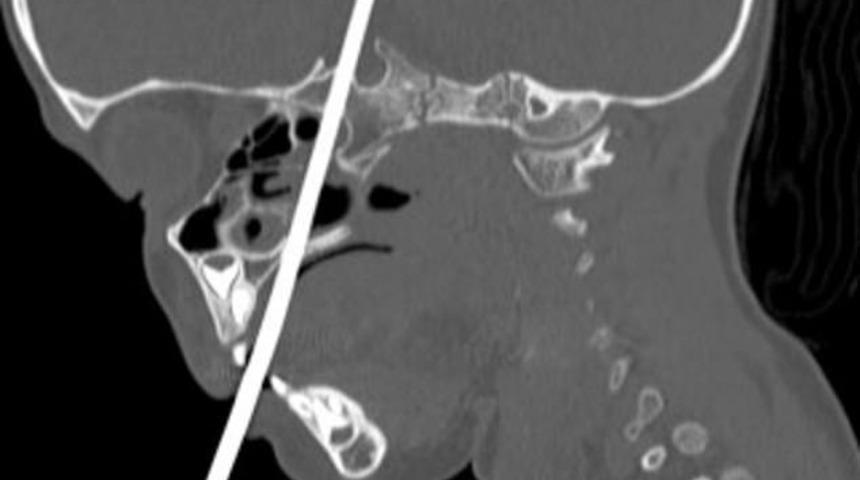

Elinde olan şiş de küçük çocuğun ağzından girip ense kökünden çıktı.

Küçük çocuk apar topar hastaneye kaldırıldı.

İlk tetkiklerde şişin beyne saplanmasına rağmen beyinde kalıcı bir tahribata neden olmadığı ortaya çıktı.